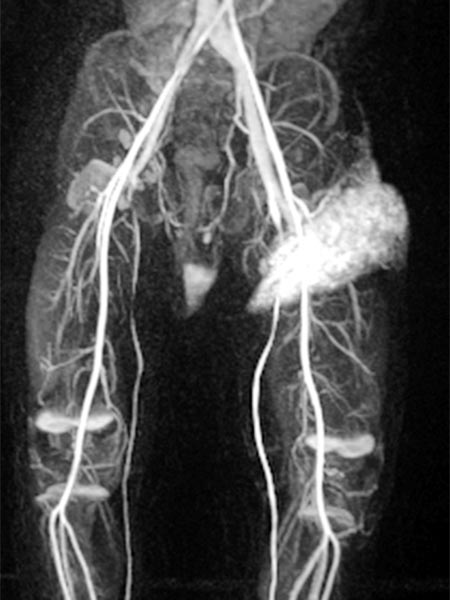

Auch in der Übersichtsangiographie über die linke Arteria iliaca externa zeigt sich keinerlei Perfusion des Tumors mehr, die Tumorvaskularisation ist somit erfolgreich superselektiv vollständig verschlossen. Alle nicht pathologischen Arterien sind erhalten.